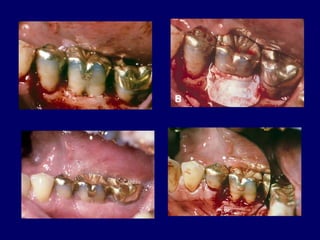

Root Resection

 Indicated in multirooted

teeth with Grade II or

grade IV

 May be performed on vital teeth or

endodontically treated teeth.

 It is preferable to perform endodontic therapy

before resectioon.

 WHICH ROOT TO REMOVE .

 Remove the root that will elimnate the

furcation .

 Remove the root with greatest amount of

bone loss and attachment loss.

 Remove the root that best contributes to

the elimnation of periodontal problems of

adjacent teeth.

 Remove the root with greatest number of

anatomic problems .